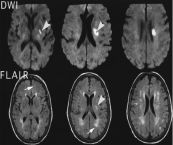

Nhồi máu não chiếm tỷ lệ khoảng 80% đột quỵ não, 20% còn lại là chảy máu não, chảy máu dưới màng nhện. Bài viết này sẽ nói rõ hơn về hội chứng Nhồi máu não ổ khuyết cạnh não thất bên phải. Mời các bạn tham khảo!

Nhồi máu não chiếm từ 70-80% các trường hợp đột quỵ nhưng có thể chữa khỏi trong khi bệnh nhân bị xuất huyết não dễ tử vong hoặc tàn phế. Để hiểu rõ hơn về bệnh lý này, mời các bạn cùng tham khảo những thông tin dưới đây nhé!